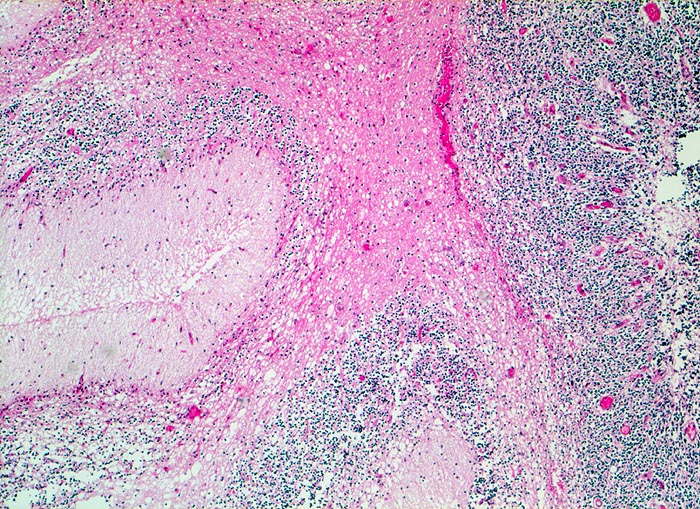

Kleinhirn

Normalbefund

Kleinhirn

Nervensystem

Medulloblastom angrenzend an das Kleinhirn und die Medulla oblongata

Knabe mit Kopfschmerzen und morgendlichem Erbrechen ohne Übelkeit

Histologie

50

7

männlich